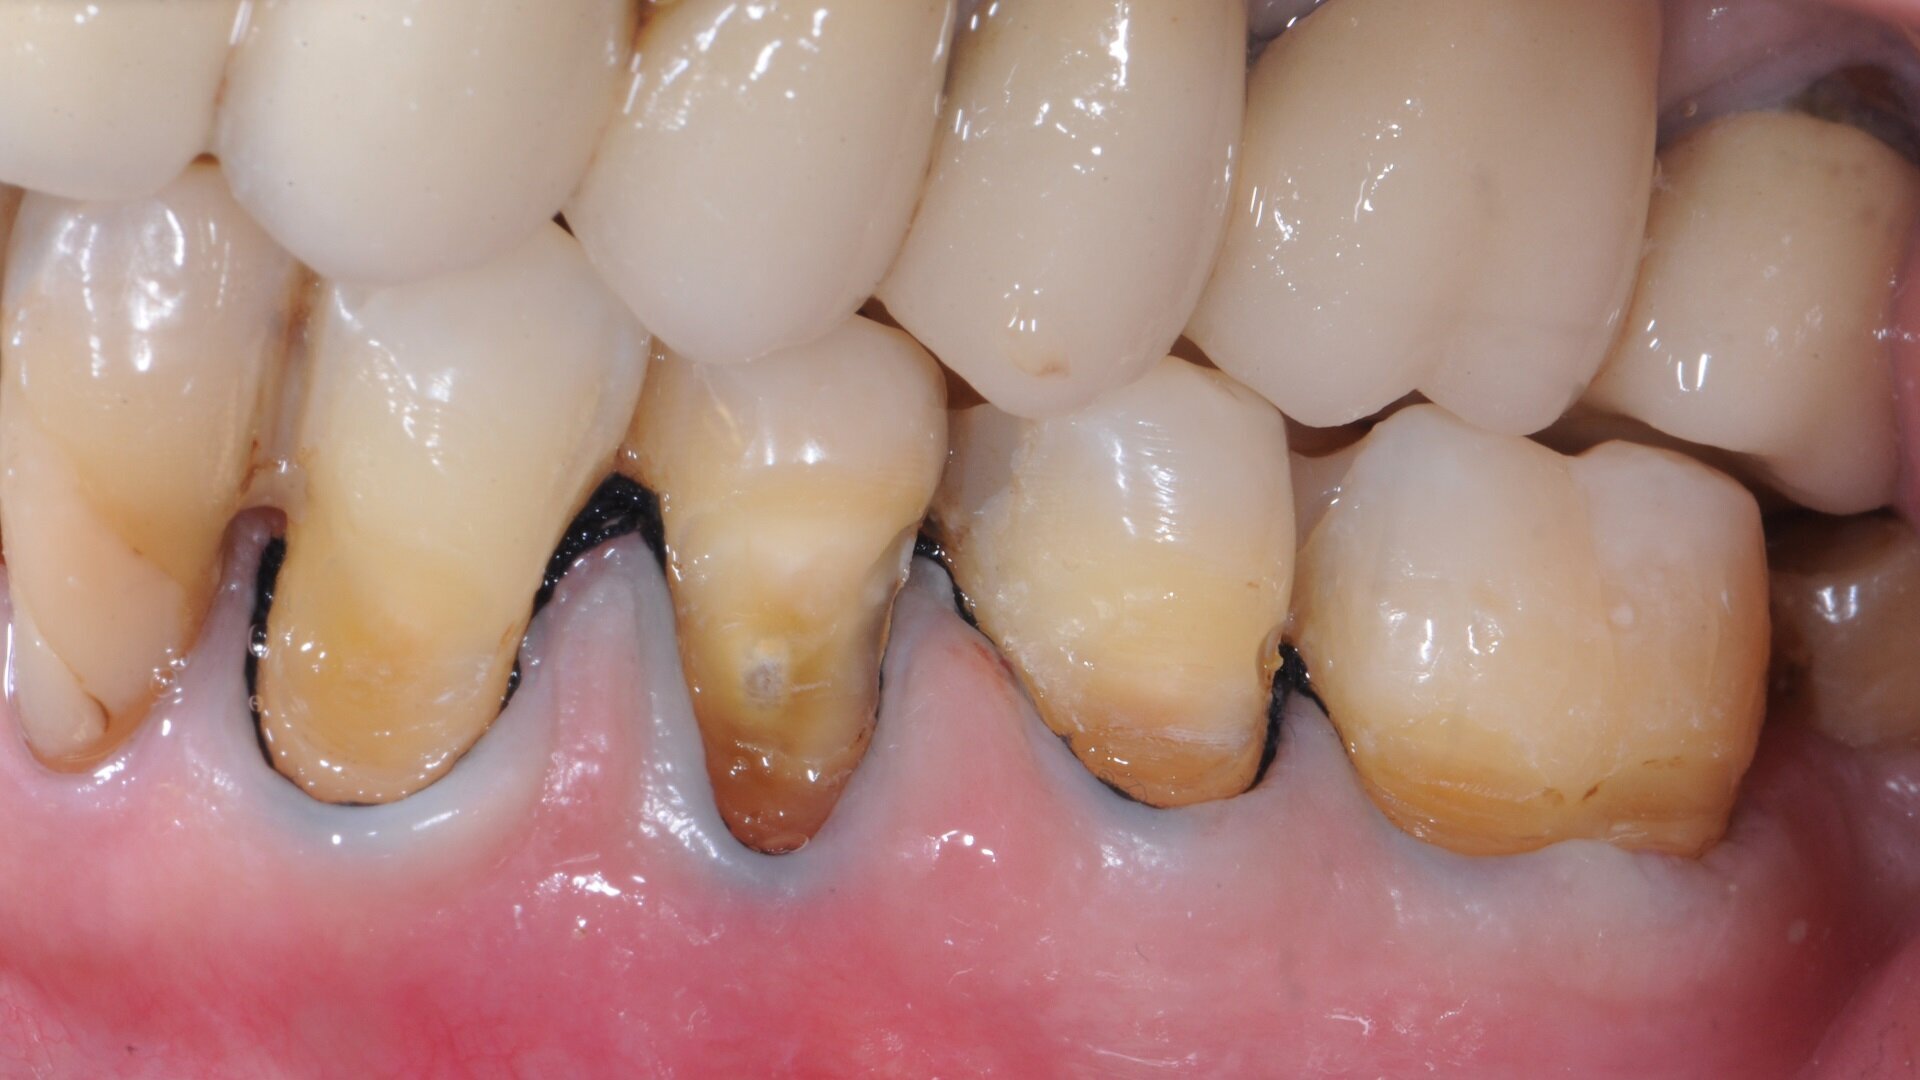

Fig. 4: Class I restoration on tooth #47 with marginal discoloration and recurrent caries prior to treatment.

Occlusal-proximal lesions (Figs. 4–9)

In contrast to cervical lesions, glass ionomers were not considered for restoration of posterior, load-bearing and proximally extended cavities in the past. As mentioned, their limited flexural strength and abrasion and erosion resistance have often compromised the success and survival of glass ionomer restorations for this indication. However, with the glass hybrid materials, a number of clinical studies have now refuted that notion. Two recent randomised trials are particularly noteworthy.

In the first trial, a glass hybrid (EQUIA Forte), a bulk fill composite resin (Filtek Bulk Fill Posterior Restorative, 3M) and a micro-hybrid composite resin placed incrementally (Charisma Smart, Kulzer) were compared.8 In total, 109 teeth in 54 rather young patients (31 female, 23 male; mean age: 22 years) with two-surfaced (mesio-occlusal, disto-occlusal) cavities in permanent teeth were randomly restored. The restorations did not extend towards cusps and all cervical margins were placed in sound enamel (i.e. not subgingivally). After caries removal and minimally invasive preparation, the materials were placed. After up to 24 months, 84 restorations were evaluated using the modified USPHS criteria. Composite restorations showed better anatomical form, contact points, colour matching, surface texture and overall survival compared with the glass hybrid restorations.